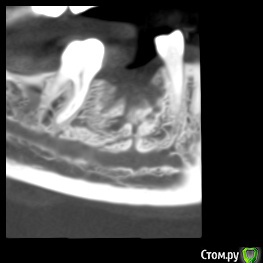

dentikl Опубликовано 26 ноября, 2019 Поделиться Опубликовано 26 ноября, 2019 В августе планировали имплантацию отсутсвующего 46 .Сделали кт,почистили .3 месяца. Ждать или уже ставить? Ссылка на комментарий

Irouil Опубликовано 26 ноября, 2019 Поделиться Опубликовано 26 ноября, 2019 Ставить 2 Ссылка на комментарий

red_butler Опубликовано 26 ноября, 2019 Поделиться Опубликовано 26 ноября, 2019 +1 ставить 1 Ссылка на комментарий